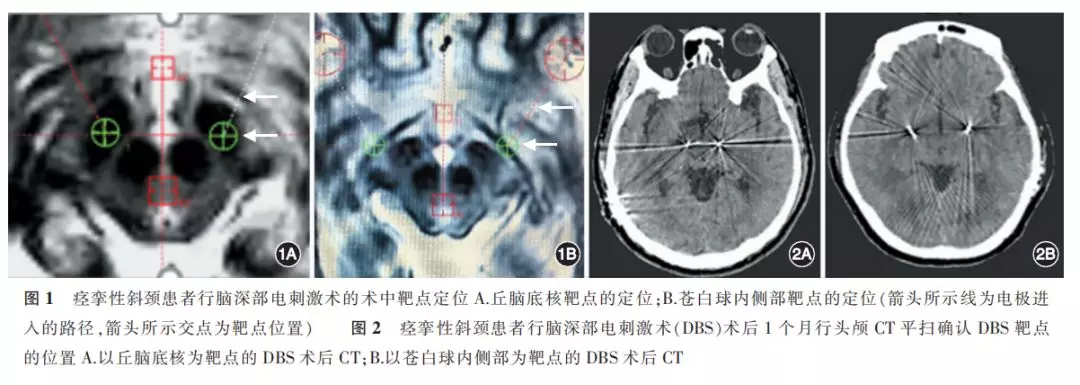

安装Leksell头架,行头颅MRI或CT扫描。利用MRI图像或CT-MRI融合结果进行靶点定位(图1)。GPi靶点一般位于前联合(anterior commissure,AC)-后连合(posterior commissure,PC)连线外侧18~22 mm、AC-PC连线中点前方2 mm、AC-PC连线下方6~9 mm;STN靶点一般位于AC-PC连线外侧12~14 mm、AC-PC连线中点后方2~3 mm、AC-PC连线下方4~6 mm。通过记录单细胞放电和局部场电位,进一步明确靶点的位置。植入电极后,予试验性电刺激进行测试。刺激脉宽为60~90 μs,频率为130~150 Hz,电压为0~4 V,由小到大逐渐增加,明确有无不良反应。如出现不良反应则更换靶点的位置,若无明显不良反应则植入电极,外接临时测试线。术后当日进行CT检查,明确有无颅内出血。于术后第2天开始进行临时测试,根据效果调整刺激参数或更换刺激触点。测试患者症状的改善情况以及有无不良反应。

(3)靶点确认:

对部分患者术后1个月开机时进行头颅CT平扫(层厚为0.625 mm),确认靶点的位置(图2)。若靶点的位置不明确,则进一步行MRI检查;若靶点位置无误,则开机进行规律程控治疗;若靶点位置欠准确,则根据程控反应情况决定下一步治疗方案。14例患者中,7例采用以丘脑底核(STN)为靶点的DBS(简称STN-DBS),且均为双侧STN-DBS;7例采用苍白球内侧部(GPi)为靶点的DBS(简称GPi-DBS)。6例患者行双侧GPi-DBS,1例行单侧GPi-DBS。